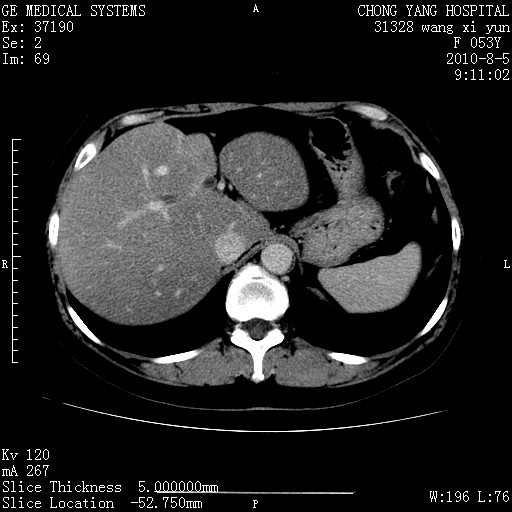

标题: CT28214:F41Y 血尿二十天,建议盆腔平扫加增强。

胆管细胞ca?

1)考虑肝左叶胆管细胞癌。2)脂肪肝。

支持胆管细胞ca。